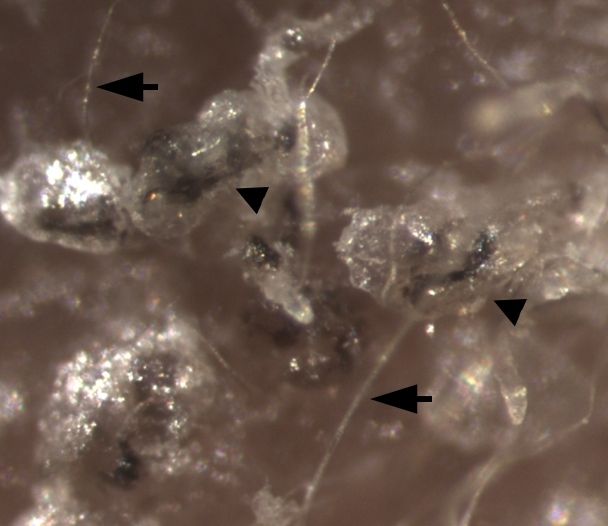

箭头所指为小鼠天然毛发,三角形标记为上皮干细胞分化后产生的毛囊

分化后的上皮干细胞被移植到老鼠的皮肤细胞中,并产生与人体表皮相似的皮肤,毛囊也清晰可见。实际上,这些新的皮肤表面也长有毛发。